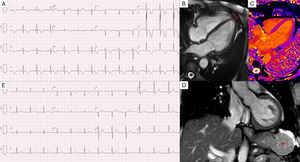

(A) ECG showing high-voltage R waves and global symmetrical T-wave inversion. (B) Cardiac MRI cine b-SSFP four-chambers image showing non-thickened biventricular walls (e.g. interventricular septum of 7 mm) and no signs of apical hypertrophy (red arrow). Tissue characterization sequences including STIR T2-weighted imaging, native T1 mapping (C), and LGE were unremarkable, showing no evidence of myocardial edema, fibrosis, or infiltration. (D) Cardiac MRI coronal TRUFI image showing a round and relatively homogeneous solid lesion in the greater gastric curvature (red asterisk). (E) ECG at one-year follow-up demonstrating complete resolution of the previously observed R and T wave abnormalities.

Multimodal imaging, including transthoracic echocardiography, cardiac computed tomography (CT), and magnetic resonance imaging (MRI), revealed no structural heart disease, ventricular hypertrophy, or myocardial/pericardial inflammation (Figure 1B and C). A thoracoabdominal CT identified a 5.5 cm homogeneous contrast-enhanced lesion on the greater curvature of the stomach. A subsequent CT demonstrated rapid tumor growth in close anatomical proximity to the heart, without evidence of compression or displacement of cardiac structures. The mass showed defined demarcation from the surrounding tissues on MRI (Figure 1D). A CT-guided biopsy identified a gastrointestinal stromal tumor (GIST). Following subtotal gastrectomy, pathology confirmed a low-risk GIST with clear margins. Postoperative follow-up at six months revealed no residual disease, and serial ECGs over the following year demonstrated full normalization of prior abnormalities (Figure 1E).